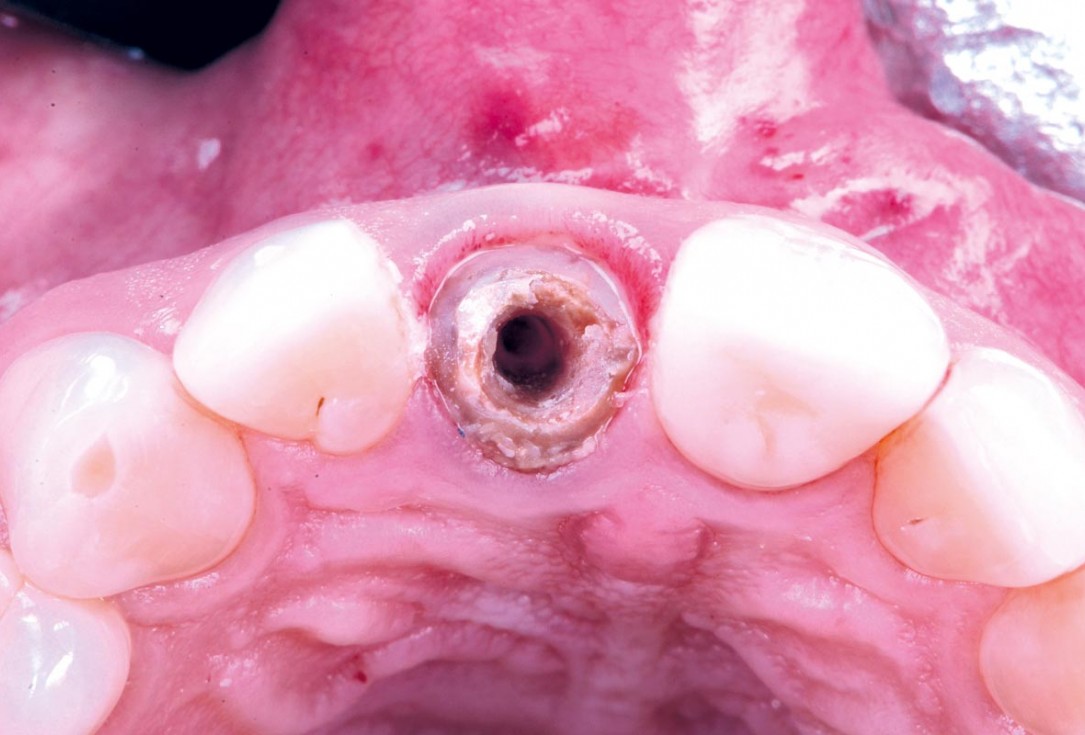

Initial clinical situation - Central incisors with dental destruction and periapical pathology